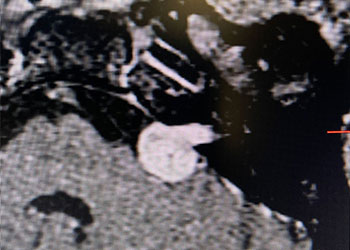

Endovascular:

Hydrocephalus and Brainstem Tumor

Author: Jonathan L. Brisman M.D., F.A.C.S., Read More!